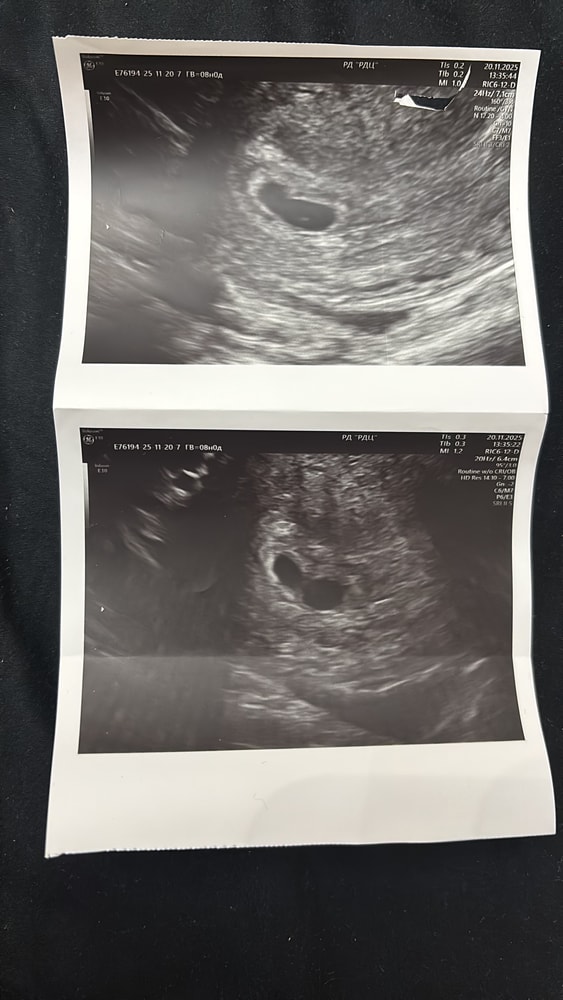

Результаты узи на 8 неделе и 10 неделе

Помогите пожалуйста кто сталкивался , что это может значить ? Там все таки один плод ?